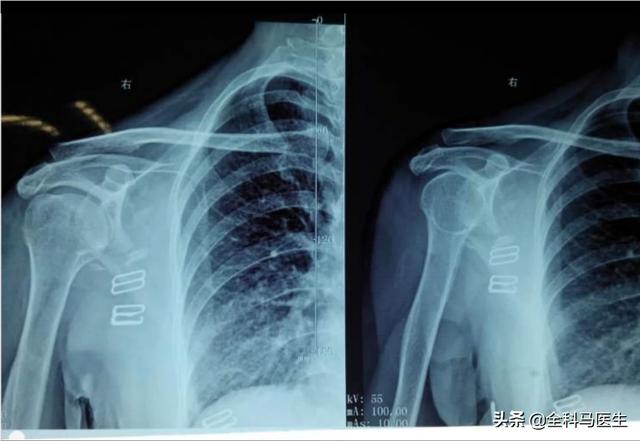

2. die Erkrankungen der Gallenblase

Viele Menschen für die rechte Seite des Schulterblattes Schmerzen dachte nur, es war gefrorenen Schulter oder Müdigkeit, aber nicht wissen, dass Gallenblase Krankheit (Cholezystitis, Gallenblase Steine) kann auch dazu führen, dass die Entstehung der rechten Seite des Schulterblattes und Rückenschmerzen, dieses Symptom wird als Schmerzen, das heißt, die Gallenblase Schmerzen, die durch die Nerven, die in die Entstehung der rechten Seite der Schulter und Rücken und der rechten Seite des Arms, die Finger zu sein schien Schmerzen Taubheitsgefühl.